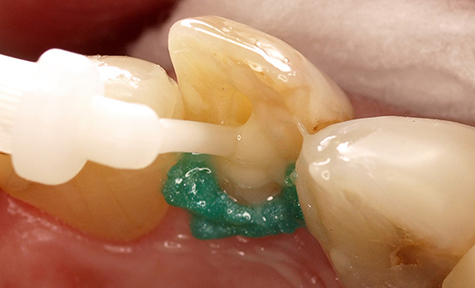

Het gebruik van Futurabond U in de Self-Etch-techniek is zinvol in klinische casussen waarbij alleen de dentinesubstantie hoeft te worden geëtst en/of het glazuurgebied geen intensieve en zeer agressieve conditionering nodig heeft. Aan de hand van de klinische casus van een 42-jarige patiënt worden de bevestiging van een stift en het gebruik van Futurabond U na een zeer ruime caviteitpreparatie voor een prothetische restauratie getoond, waarbij grotendeels alleen dentine werd geëtst. Door speciale applicators (Endo Tim, VOCO) voor gebruik in het wortelkanaal kan het adhesief ook daar zijn volledige werking ontwikkelen, omdat een volledige bevochtiging van de kanaalwanden plaatsvindt. Het actief inmasseren van Futurabond U in alle dentine-oppervlakken in het wortelkanaal bereidt de tandstructuur optimaal voor de aansluitende bevestiging voor (afb. 4-6). Een in het wortelkanaal lastig uit te voeren uitharding met licht is bij het duaalhardende Futurabond U niet nodig.

Afb. 5: Met de speciale applicator EndoTim (VOCO) wordt het wortelkanaal betrouwbaar bevochtigd met Futurabond U

Afb. 6: Applicatie van het opbouw- en bevestigingsmateriaal Rebilda DC (VOCO)